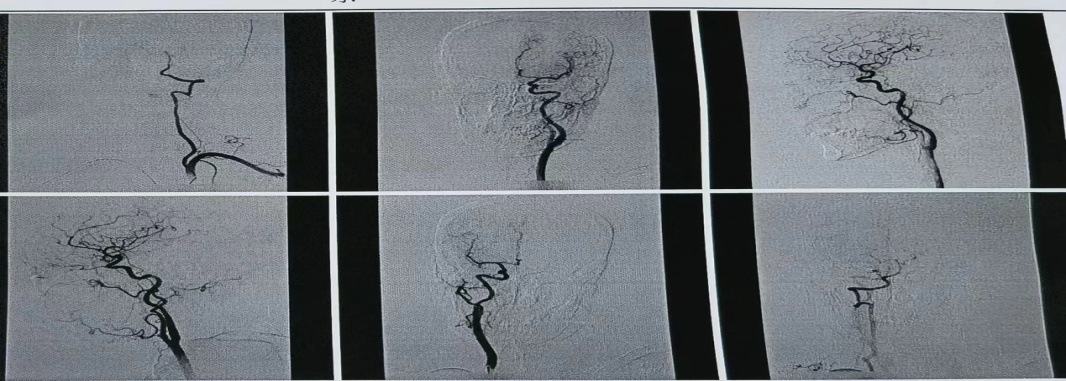

患者以肢体无力就诊,颅脑核磁提示颅内动脉多发节段性狭窄,明确诊断为多发脑梗死。王乐医师指导受援科室介入团队采取经“桡动脉全脑血管造影术”,明确患者脑血管狭窄情况。取得患者及家属充分知情同意后,手术用时不到1小时,过程顺利,患者生命体征平稳,术后即刻下床,活动自如。术后6小时拆除桡动脉压迫器,穿刺处无渗血渗液及硬结,搏动正常,患者无任何不适。

全脑血管造影术是评估脑血管的“金标准”。经桡动脉全脑血管造影术是近年来较先进的脑血管检查技术,为脑血管疾病的诊断和治疗提供重要依据。经桡动脉穿刺较传统经股动脉穿刺具有以下优势:一、穿刺点损伤小,术中及术后并发症少,术后护理方便安全;二、术后患者即刻下床活动,舒适度好,易于接受,尤其对于肢体瘫痪或高龄的老年人;三、术后下肢不需长时间制动,避了下肢深静脉血栓的形成,不影响患者康复锻炼及其他治疗。

黑料网神经内一科拥有一支水平先进、人才梯队合理的脑血管病介入专家团队,每年开展的脑血管疾病介入诊疗手术在全省名列前茅,开展经股动脉和桡动脉脑血管造影术、颅内外动脉狭窄球囊成型及支架植入术、颅内动脉瘤及脑动静脉畸形介入治疗、超早期脑梗死动脉溶栓和机械取栓、超时间窗(大于24小时)机械取栓、非急性颅内外血管闭塞血管内开通术、静脉窦血栓介入治疗等神经科常见及复杂介入手术,现领先并成熟开展的经桡动脉全脑血管造影术,为脑血管病患者开辟了新的检查治疗途径。